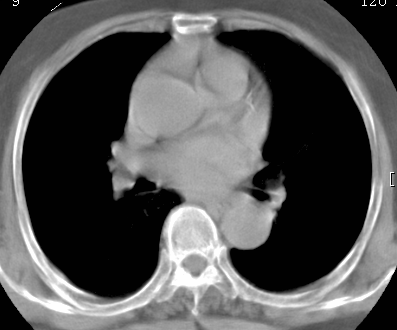

考虑1、周围型肺癌,2肺静脉畸形,前者可能大,建议增强检查。

考虑1、周围型肺癌,2肺静脉畸形,前者可能大,建议增强检查。支持!

不排除右肺下叶周围型肺癌可能。

中心型肺癌,纤支镜可帮助明确。